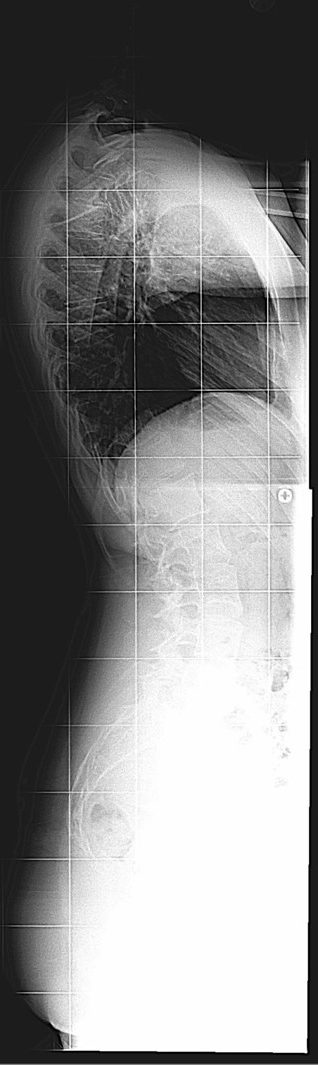

20 Yaşında Kadın Hasta

Boy: 171.3cm.

Kilo: 66kg

Rib hump lomber 10 derece

Ameliyat Öncesi

Ameliyat Sonrası